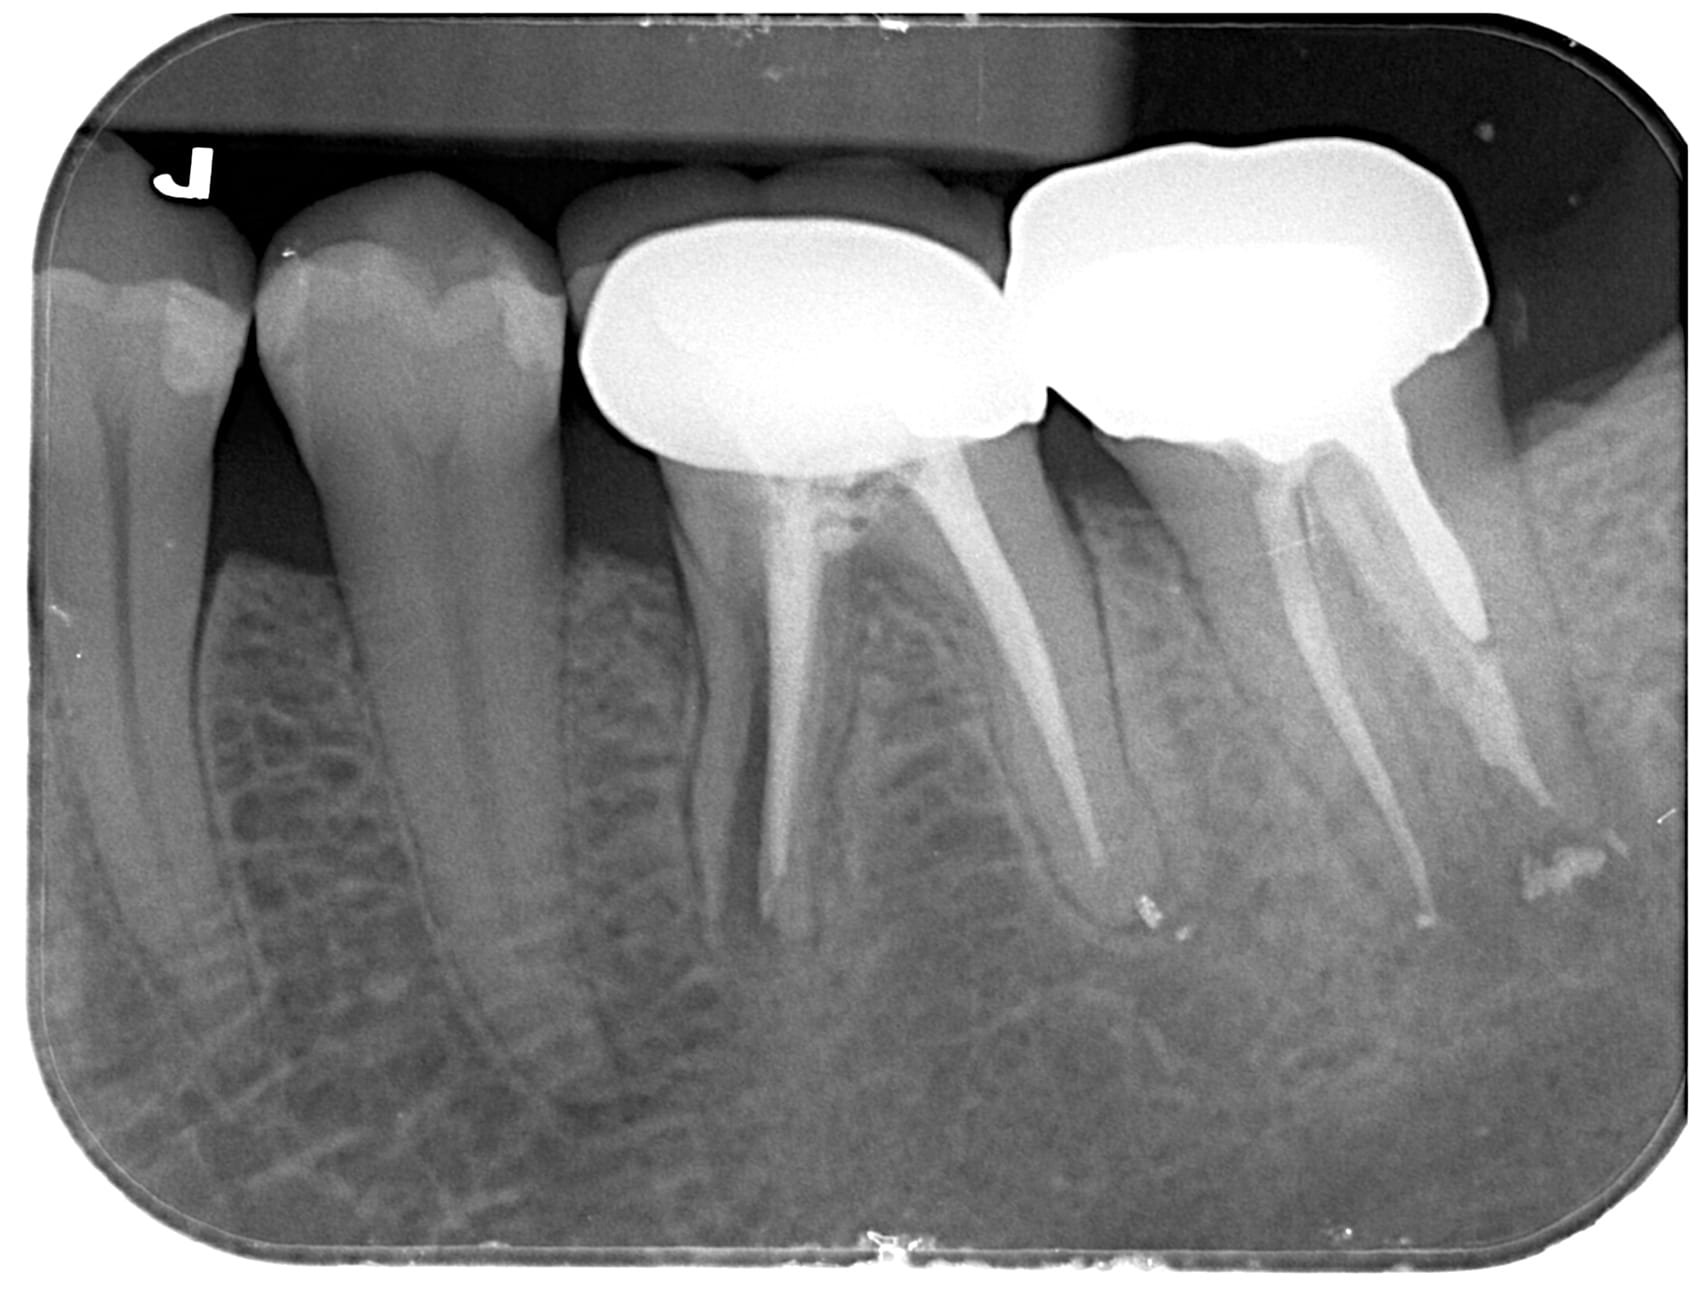

右下第一大臼齒蛀斷 原右下第一.二大臼齒假牙相連,因右下第一大臼齒蛀牙到根部,導致兩顆假牙脫落,右下